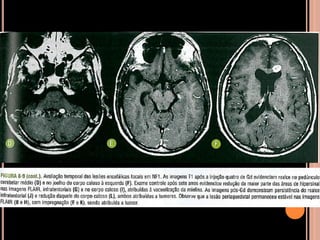

Área de vacuolização de mielina

 Origem é controversa;

 Achado típico em crianças com NF1;

 Focos hiperintensos em T2 e no FLAIR em núcleos

da base, cápsula interna, tronco encefálico e

cerebelo;

 Mais comum no globo pálido, geralmente bilateral;

NF1

Vacuolização de mielina

 Aparecimento geralmente aos 3 anos  aumenta

até os 12 anos  tendência a regredir;

 Raro observar após os 20 anos de idade;